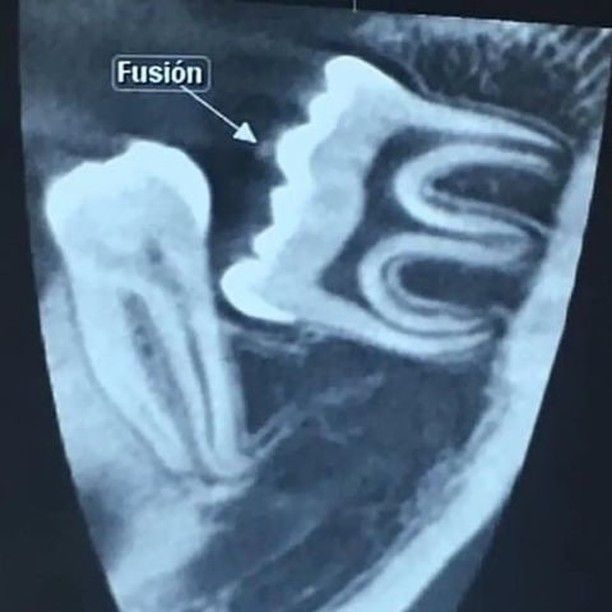

Fusion of tooth

A dental anomaly where two teeth fuse together during development

Fusion